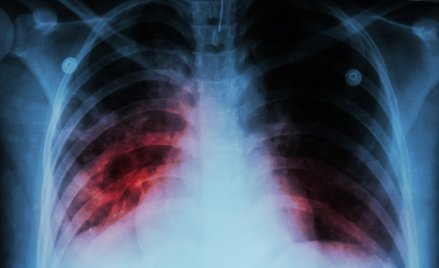

Gruźlica zmienia oblicze

Atakuje osoby starsze, coraz trudniej się leczy, nadciąga ze wschodu. Dziś Światowy Dzień Gruźlicy.

Ukraina: Oficjalnie 35 tys. pacjentów z gruźlicą. Nieoficjalnie 17 razy więcej

Ukraińskie ministerstwo zdrowia poinformowało, że obecnie w tym kraju zarejestrowanych jest 34966 pacjentów z gruźlicą, z czego ok. 8 tys. ma lekoodporną o...